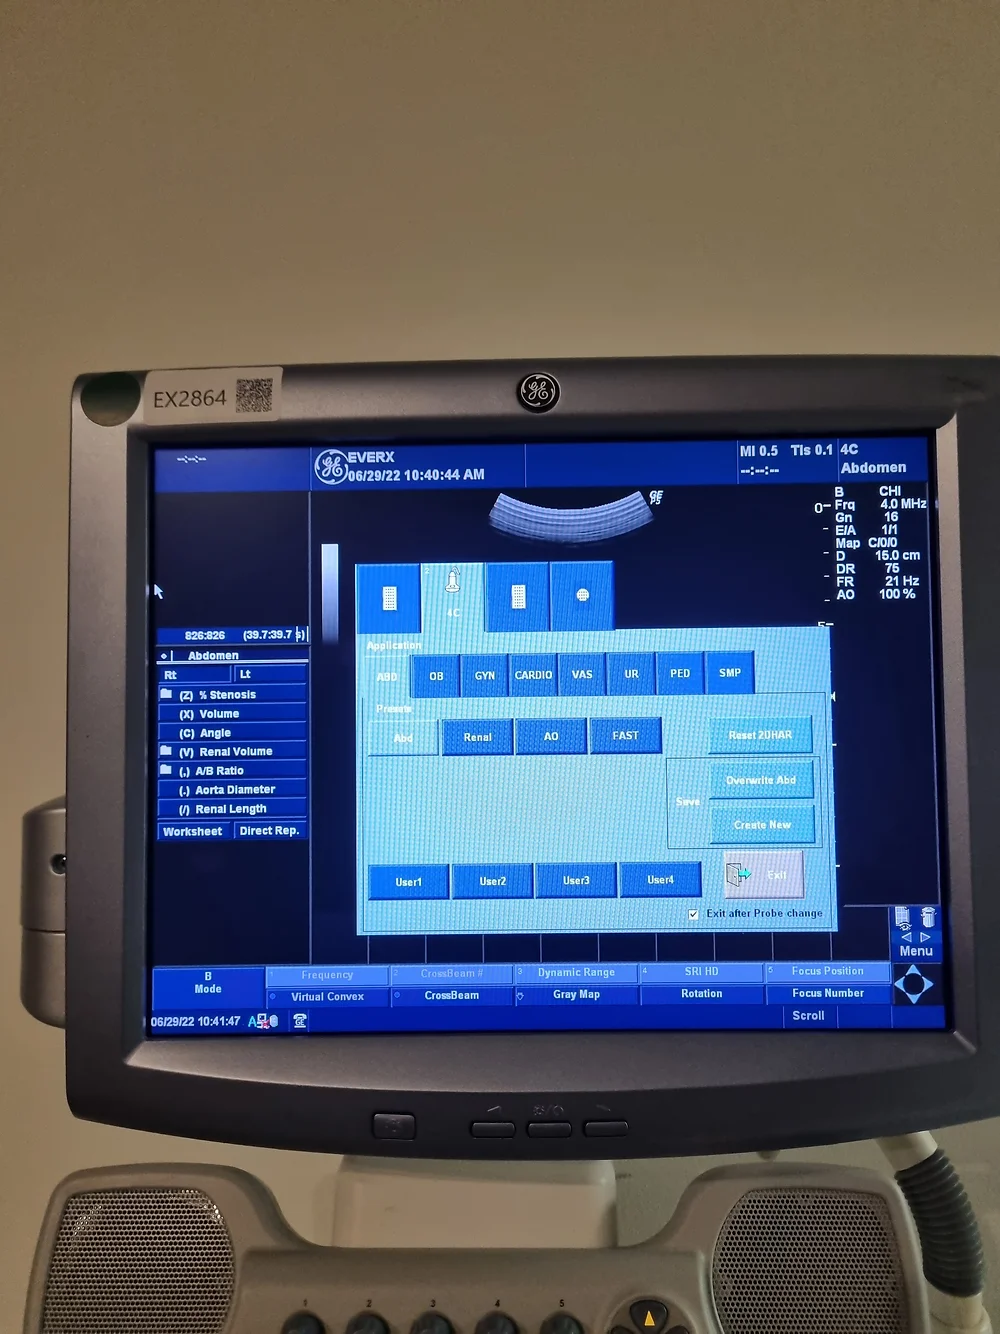

The LOGIQ P5 ultrasound system redefines compactness and efficiency while boasting a plethora of high-end features typically found in more expensive devices. Engineered for versatility and precision, this cutting-edge ultrasound scanner delivers unparalleled imaging quality across various medical specialties, including gynaecology/obstetrics, urology, cardiology, and paediatrics.

- Exceptional Performance: Despite its compact size, the LOGIQ P5 stands out as one of the most robust systems in its price range, offering features like CrossXBeam composite imaging, cardiac imaging, and speckle reduction for superior diagnostic accuracy.

- Enhanced User Experience: Navigate seamlessly through procedures with the LOGIQ P5’s intuitive interface and ergonomic design, ensuring optimal comfort and efficiency during imaging sessions.

- Comprehensive Imaging Solutions: From automatic tissue optimization to coded harmonic imaging and high pulse repetition rate, the LOGIQ P5 is equipped with a range of innovative technologies to enhance imaging performance across diverse clinical applications.